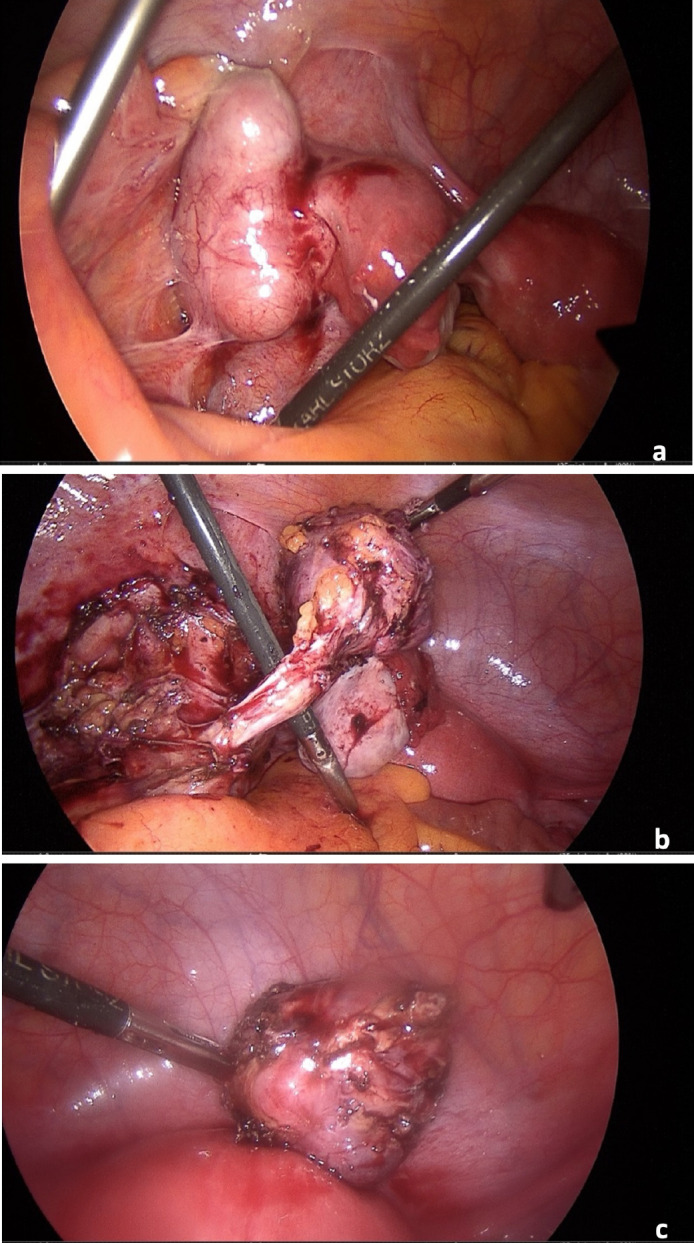

Leiomyosarcomas (LMS) arise from smooth muscle and represents only 6% of all sarcomas. LMS originating from major blood vessels, called vascular LMS, are detected mostly in the inferior vena cava. Arterial LMS are a rarity. We present a 43-year-old patient with a LMS arising from the left external iliac artery. The patient was referred to us with symptoms of left lower abdominal pain extending to the left limb and underwent a contrast computed tomography which suggested a suspicious mass near the left iliac vessels. She underwent laparoscopic excision of the tumour, whose histological examination revealed an LMS G2 arising from the external iliac artery. Immunohistochemically CD34, p53, Desmin, as well as smooth muscle actin, tested positive.

Abstract Image